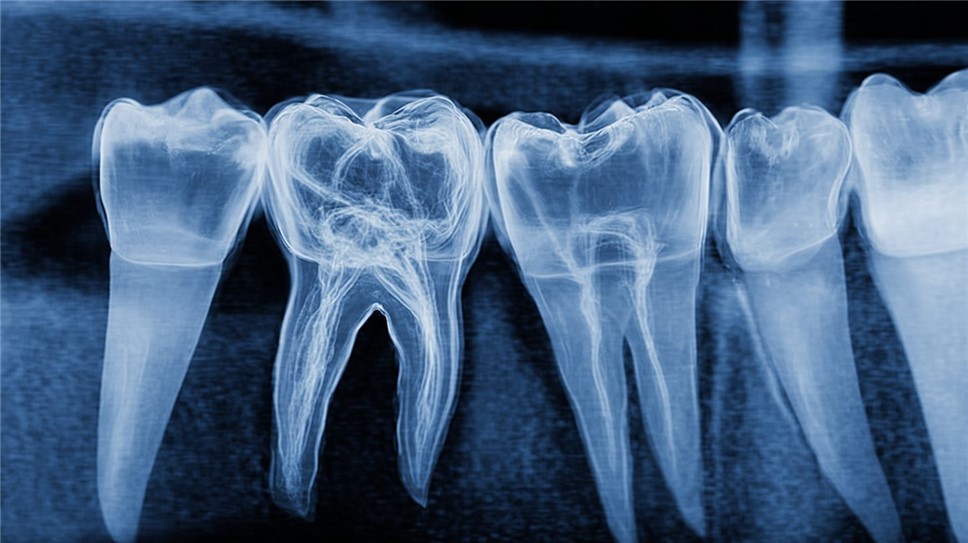

При хроническом пульпите боль становится тупой и ноющей, возникая спонтанно или при надавливании, и может иррадиировать в ухо или челюсть. Ограничением самостоятельной оценки является субъективность ощущений: гипотеза о пульпите требует подтверждения рентгеновским снимком для оценки распространения инфекции. В Санкт-Петербурге, согласно нормам Сан Пи Н 2.1.3.2630-10, клиники используют цифровую радиографию для точной визуализации.

Инструментальные методы усиливают диагностику: рентгенография в прицельной проекции выявляет периапикальные изменения в 60% хронических случаев. Цифровой рентген, внедрённый в 90% российских клиник по стандартам Росздравнадзора 2025 года, снижает дозу облучения на 70% и позволяет оценить глубину кариеса. Для сложных анатомий, как у многокорневых зубов, применяется конусно-лучевая компьютерная томография (КЛКТ), точность которой достигает 95% по данным исследований в Новосибирском НИИ.

Пример рентгенограммы, демонстрирующей изменения в области корня зуба при пульпите.